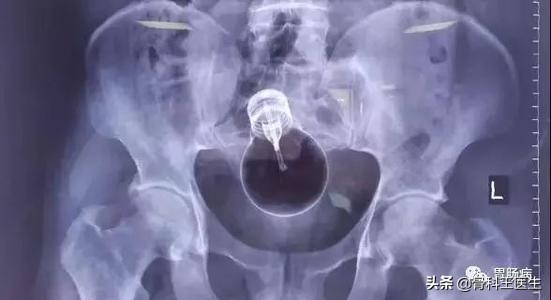

5、阴道、尿道取异物:

负责任的讲,肛门能进去的阴道都能塞进去:

我只发两张图,笑笑不说话:

为什么会把异物塞进尿道,为什么会有人往尿道里塞异物